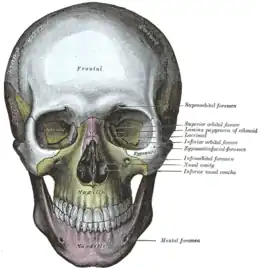

On compte 7 os structuraux. Premièrement, des os larges, plats ou convexes :

- 1 os frontal, en avant du crâne, formant le front et la voûte orbitaire ;

- 1 os occipital, formant l'arrière et la base du crâne, joignant le crâne à la colonne vertébrale ;

- 2 os pariétaux, formant la calotte crânienne et les parties latérales hautes du crâne, et situés en arrière de l'os frontal ;

- 2 os temporaux, situés sous les os pariétaux ; les temporaux sont les os les plus fragiles du crâne car les plus minces.

Deuxièmement :

- 1 os sphénoïde, médian, qui participe à la base du crâne et aux cavités orbitaires et nasales ;

- 1 os ethmoïde, entre les orbites, qui participe à la fosse crânienne antérieure par sa lame criblée et le processus crista gali, ces deux structures s'encastrent dans l'incisure ethmoïdale de l'os frontal ;

- 2 os maxillaires, qui forment la mâchoire supérieure.

Ces trois derniers associés à l'os frontal contiennent les sinus, des espaces creux remplis d'air (« espaces pneumatiques »).